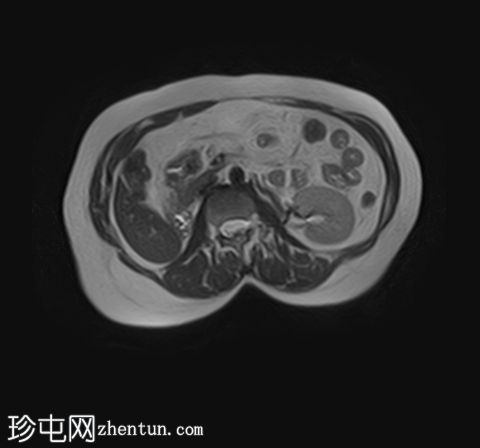

MRI

轴位T1加权像

(同相/反相)

轴位

T1加权像

脂肪抑制像

轴位T2加权像

STIR(FASE)序列

T2加权像

左侧肾上腺可见一边界清晰的病灶,大小约为3.0 × 2.4 × 2.0 cm。

化学位移成像显示,反相图像的信号强度较同相图像明显降低,与细胞内脂质含量相符。

右肾先天性缺失。左肾轻度肥大,信号强度正常。